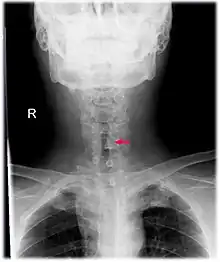

| Neck AP x-ray of patient with post-intubation subglottic stenosis, as shown by the narrowing in the tracheal lumen marked by the arrow. | |

CT scans and MRI (magnetic resonance imaging) can help in diagnosis. X-rays can determine the location and size of the narrowed airway portion. Optical coherence tomography (OCT) can help observe the progression of the injury. Esophageal pH monitoring can help detect any acid reflux, which can worsen the condition. An endoscope can be inserted and used to see the vocal cords, airway, and esophagus. Spirometry is a useful way to measure respiratory function. People affected by subglottic stenosis have a FEV1 of over 10.[2]